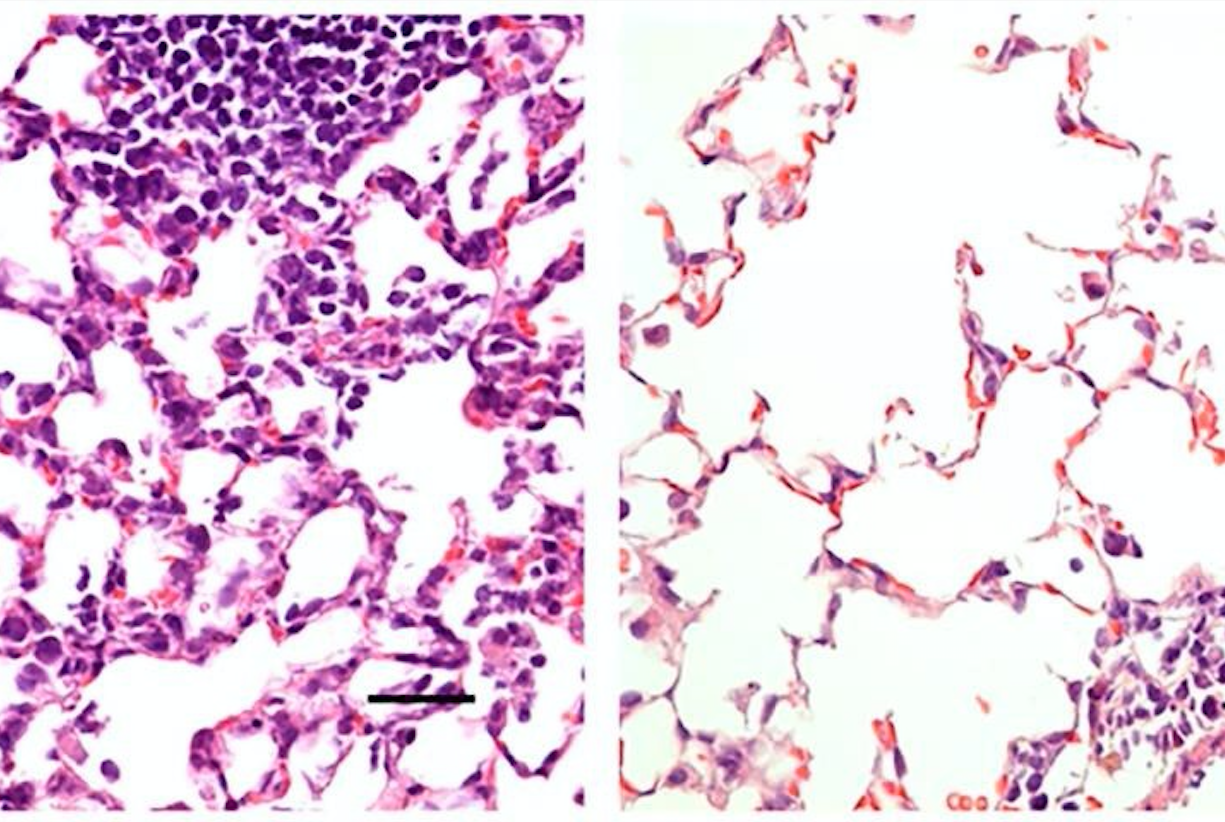

Los investigadores compararon esta vacuna administrada a los ratones de dos maneras: en la nariz y a través de una inyección intramuscular. Mientras que la inyección indujo una respuesta inmune que previno la neumonía, no previno la infección en la nariz y los pulmones. Tal vacuna podría reducir la gravedad de COVID-19, pero no bloquearía totalmente la infección o evitaría que los individuos infectados propagaran el virus.

Por el contrario, la vía de administración nasal previno la infección en las vías respiratorias superiores e inferiores (la nariz y los pulmones) lo que sugiere que los individuos vacunados no propagarían el virus o desarrollarían infecciones en otras partes del cuerpo.